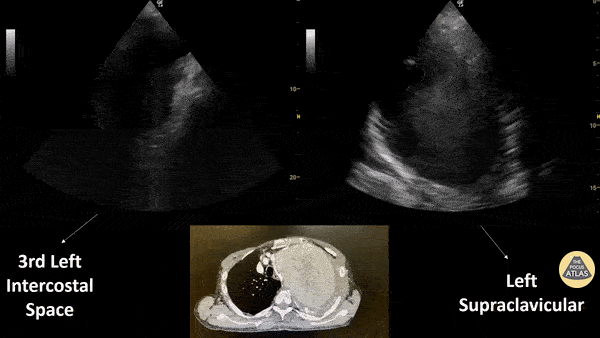

Patient with a subacute history of chest trauma (occurred approximately 30 days prior) presented reporting intermittent chest pain. He was noted in the ED to have persistent pain and to be sweating. Bedside evaluation included lung ultrasound that identified the cystic structure seen here with a hypoechoic interior with visible swirling. Chest CT shown confirmed this to be sequelae of aortic trauma. Renato Melo, Emergency Physician Brazil. PocusJedi affiliated. @Renato_Melo_